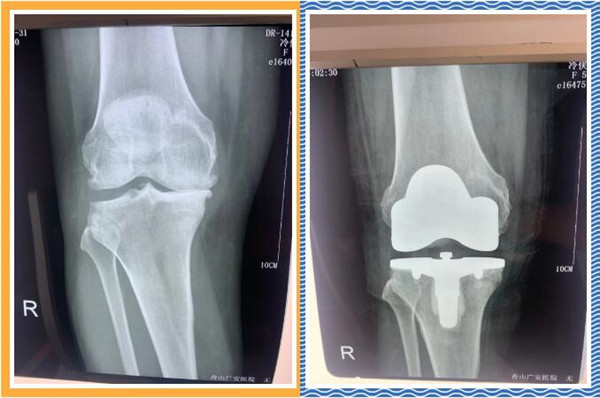

經(jīng)查體及拍片檢查后,危立軍副院長認為冷大姐是右膝關節(jié)嚴重磨損,是年輕時干重體力工作導致關節(jié)提前磨損,年紀是輕了一點,但關節(jié)置換是一種相對較好的辦法,可早期恢復關節(jié)正常,改善生活質量,建議其入院并接受人工膝關節(jié)表面置換手術。。

三天后,冷大姐接受了右膝關節(jié)置換手術。手術由危立軍副院長主刀,在關節(jié)鏡下順利完成。術后,冷大姐恢復良好。同時,在經(jīng)過院部協(xié)商后,減免了冷大姐的部分手術費用和住院治療費用。出院那天,冷大姐熱淚盈眶,感謝的話說了又說。